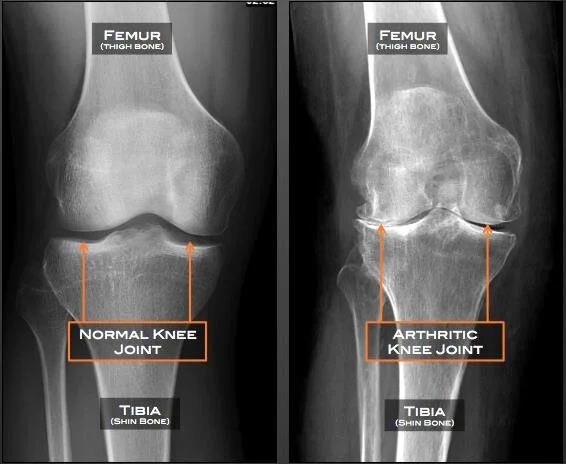

Osteoarthritis (OA) is the gradually wearing and degeneration of the cartilage in a joint. It’s considered a “wear-and-tear” process and is common in people over the age of 50, but can occur in younger individuals. As the cartilage wears, there is a loss of joint space and rubbing resulting in bone-on-bone contact and possibly bone spurs. OA is slow developing and the resulting pain and inflammation will gradually worsen.